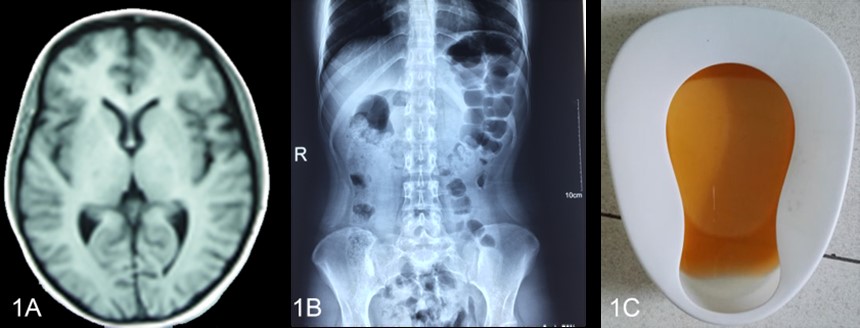

A 头颅MRI显示正常 B腹部平片示肠胀气 C 棕色尿液

图1-1 先证者发作的临床资料

先证者2016年4月开始发病,先后多家医院诊断为“胃肠炎”、 “不完全肠梗阻”、“癫痫”,并伴有低钠血症、低钾血症、高胆红素血症、持续性的下肢无力和疼痛,窦性心动过速,高血压、贫血、肝损伤,胰酶升高。在住院期间,曾排出棕色尿液促进了对AIP的诊断。最终,尿PBG阳性和尿铅阴性确认了AIP。